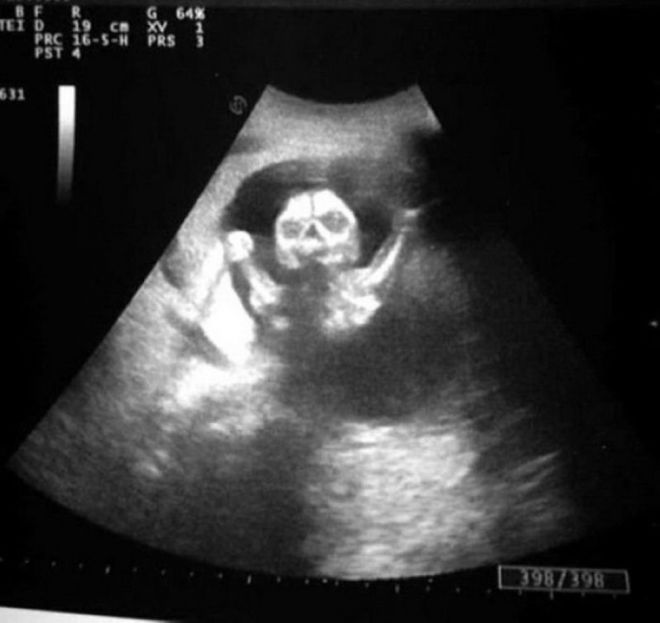

Հմմ, սա իսկապե՞ս փոքրիկ երեխա է։